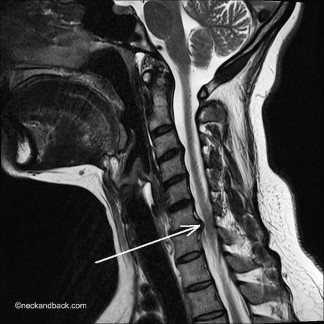

Hình 1.4. MRI cắt dọc cột sống cổ ở người trẻ có cột sống cổ bình thường

Ảnh T1W ở một người khác thấy đĩa đệm đồng tín hiệu không vượt quá bờ thân đốt sống. Bờ trước và bờ sau tủy sống lượn đều không bị đẩy lõm |